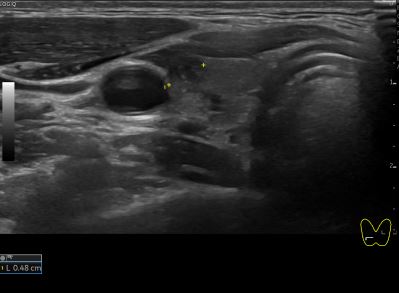

아산유외과개원후 142번째 갑상선암진단

상기환자 외부건진 갑상선 이상소견으로 세침검사위해 내원하신 20대 후반 여성분으로

의심스러운 갑상선 우엽 세포검사후 갑상선암으로 진단되었습니다